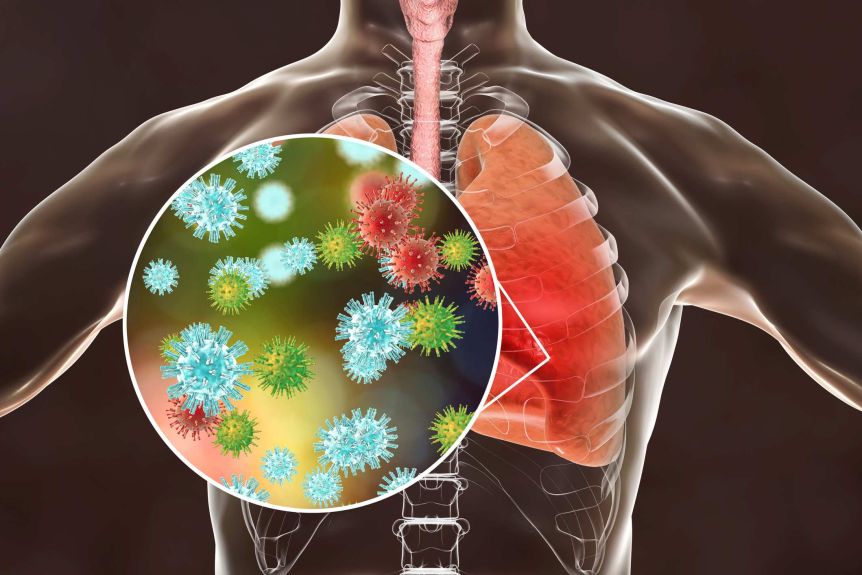

قسمت 34: پنومونیهای باکتریایی و ویروسی و تفاوت آنها با پنومونی کووید-19

پنومونیها بر اساس نوع عامل ایجادکننده و محل عفونت طبقهبندی میشوند. علائم و نشانههای پنومونی با توجه به عامل ایجادکننده آن، از خفیف تا شدید متفاوت است. تنگی نفس، سرفه (ممکن است همراه خلط باشد)، درد قفسه سینه هنگام تنفس و سرفه، سرگیجه ، گیجی یا تغییر سطح هوشیاری (در افراد بالای 65 سال)، خستگی، تب، لرز، تعریق، تهوع، استفراغ و اسهال از علائم شایع پنومونی میباشد.

قسمت 1: اهمیت انجام آزمایشهای سرولوژیک کووید

کرونا ویروسها از پاتوژنهای مهم در انسان و حیوان هستند. بیماری ناشی از کرونا ویروس جدید با نام کووید-19 به سرعت در دنیا گسترش یافت که نتیجه آن همهگیر شدن بیماری در سطح جهان بود. اعضای این خانوادهی ویروسی علاقه زیادی به لانهگزینی در ریهها دارند و تقریبا در اکثر موارد اولین ارگان درگیر در این بیماریها، ریهها هستند. ریهها متعاقب آلودگی با این ویروس دچار تخریب میشوند. نفوذپذیری رگهای ریه افزایش پیدا کرده و باعث نشت مایعات از مویرگها به فضاهای تنفسی آلوئولها میشود. |